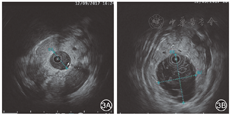

患者女,60岁,因"间断腹痛、腹胀5年余,加重10 d"收入院。患者5年前无明显诱因突发腹痛、腹胀,伴恶心、呕吐,就诊于当地医院,查血清淀粉酶、脂肪酶均升高,上腹部CT提示胰腺炎,诊断为"急性胰腺炎",对症治疗后好转出院。此后平均每年发病1~2次,近2年每次发病时血清淀粉酶、脂肪酶均升高,CT或MRI提示胰腺炎,诊断为"急性胰腺炎",并予对症处理后好转出院。10 d前无明显诱因再次突发腹胀、腹痛,呈持续性并进行性加重,向肾区放射,查血清淀粉酶980 U/L,经当地治疗症状略有减轻,后转入我院。患者既往有胆囊结石病史10余年。入院体检:痛苦面容,巩膜无黄染,心肺(-),腹软,中上腹压痛,无反跳痛,肠鸣音减弱。入院后查血常规、肝功能、肾功能、血脂、电解质正常,血清淀粉酶157 U/L,脂肪酶2 239 U/L,C反应蛋白9.10 mg/L。上腹部彩超示:胰腺炎,胰腺主胰管扩张,部分扩张呈囊状。上腹部CT提示胰腺炎,主胰管扩张,胰尾部假性囊肿(?)。MRCP示胰腺体积增大,胰管扩张,并胰尾部异常信号,考虑慢性胰腺炎并假性囊肿(?)。临床诊断为急性复发性胰腺炎,胰腺假性囊肿(?)。给予禁食、胃肠减压、抑制胰酶分泌、抑制胰酶活性、抑酸、抗炎、补液等治疗。入院2 d后行ERCP和胰管腔内超声检查术(IDUS):十二指肠镜(日本Pantax公司3790K)进镜至十二指肠降段内侧,见副乳头增大,开口呈鱼嘴样,有白色黏冻样物流出(图1A),主乳头形态正常,绒毛状开口(图1B)。使用三腔切开刀(美国COOK公司)经主乳头胰管插管成功后,注入适量造影剂(碘海醇),X光透视下见胰头段胰管无扩张,头体交界处逐渐变细至截断,胰体尾部胰管不显影(图2A);三腔切开刀+导丝(日本Olympus公司)经副头插管,导丝插管成功后,经切开刀注入适量造影剂,X光透视下见背侧胰管全段显影,胰管明显扩张,最粗直径约1.0 cm,胰管腔内可见大量絮状不均匀充盈缺损影(图2B),胰尾部胰管见囊状扩张,导丝在囊腔内盘曲(图2C)。经副乳头插入20 Hz可通导丝超声探头(日本Olympus公司),超声显示背侧胰管扩张,直径约7.7 mm,胰管内见大量絮状不均匀回声(图3A),胰尾部探及囊状扩张,最大横径约17.7 cm×13.6 cm,内部充满类圆形葡萄样增生物,呈边缘高回声、中央低回声改变(图3B)。IDUS术后,经导丝置入三腔切开刀,行副乳头切开术(图4A),切开后经导丝置入取石球囊,取出大量白色黏冻样物(图4B),然后经导丝置入鼻胰管。诊断:胰腺导管内乳头状黏液瘤(IPMN),胰腺分裂症(PD)。ERCP术后给予生长抑素、抗炎、营养支持等治疗,患者恢复良好,顺利出院。患者拒绝接受外科手术切除治疗,以随访为主。术后6个月复查MRCP见:胰管正常,无明显扩张,胰尾囊状扩张。随访至今,患者未再发生胰腺炎。

PD合并IPMN的报道较少,相比刘枫等[11]和别里克等[12]的2篇个案报道,本例在诊断和治疗中均有所不同。在诊断方面,本例病程较长,且反复发作急性胰腺炎(2~3次/年),符合急性复发性胰腺炎的诊断,在复发间期复查CT、MRI,胰腺形态正常,胰管无扩张,胰尾囊状扩张,辗转数家医院,均考虑慢性胰腺炎合并假性囊肿,体现出本病具有一定的隐蔽性。本例IDUS存在以下特点:背侧胰管全程扩张,管壁无异常增厚;病变处呈囊肿扩张;囊内见大量边缘高回声、中央低回声的葡萄样类圆形增生物。这与别里克等[12]报道的IDUS图像略有不同,但与其描述的胰管镜下观察到的葡萄样增生的肿瘤形态完全相同。在ERCP治疗方面,行副乳头切开术后,随访近1年患者未再复发胰腺炎,提示副乳头切开治疗IPMN合并PD引起的胰腺炎有效。其有效原因可能是副乳头切开解除了乳头开口处的缩窄,促进分泌物排出,降低胰管压力,避免了胰腺炎发生。但从远期疗效来看,仍建议患者积极行外科手术,切除胰尾病变部位。此外,由于PD恶变率低,而IPMN恶变率较高,因此,PD合并IPMN患者随访时,应主要以观察IPMN病变大小为主,定期复查CT或MRI,防止其恶变,必要时需立即行手术切除。